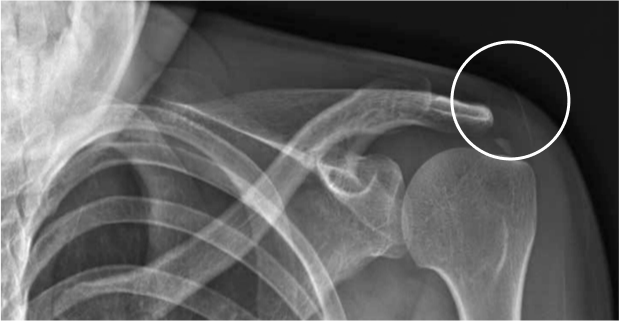

석회성물질이 어깨에 쌓여 힘줄에 통증을 유발시키는 질환입니다. 주로 30~50대에서 발생하고 있습니다.

과도한 어깨 사용으로 힘줄이 손상되어

석회가 쌓이는 것이 주요 원인!